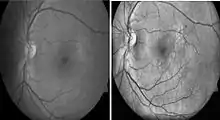

Diabetic retinopathy

Diabetic retinopathy is a disease of the retina that is diagnosed predominantly by fundoscopic images. Diabetic patients in industrialised countries generally undergo regular screening for the condition. Imaging is used to recognize early signs of abnormal retinal blood vessels. Manual analysis of these images can be time-consuming and unreliable.[75][76] CAD has been employed to enhance the accuracy, sensitivity, and specificity of automated detection method. The use of some CAD systems to replace human graders can be safe and cost effective.[76]